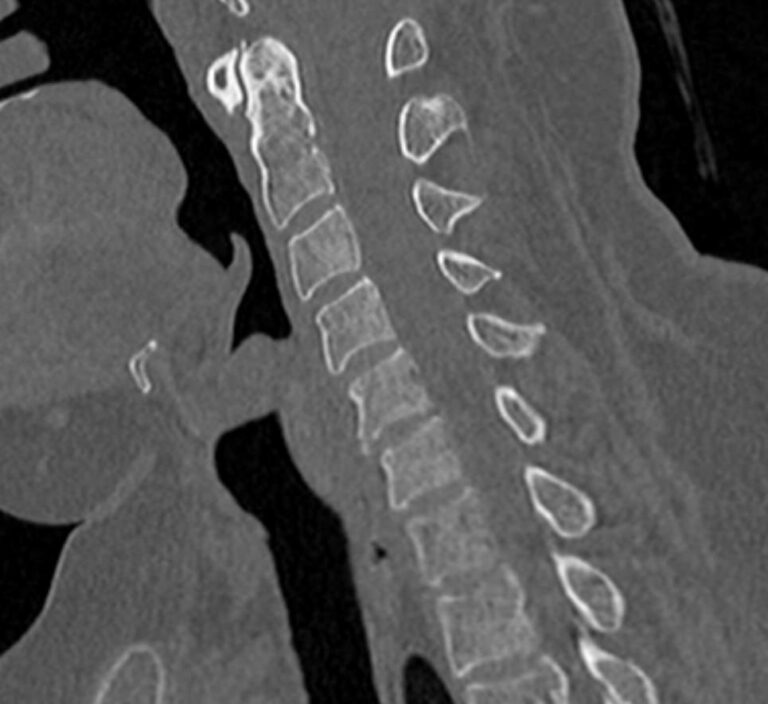

Для диагностики даже незначительных патологических изменений в различных отделах позвоночника, особенно в случае распространенного поражения, применяется один из современных наиболее информативных методов обследования – мультиспиральная компьютерная томография всего позвоночника. Методика основана на использовании проникающей способности рентгеновских лучей через органы и ткани человека и позволяет получить подробное изображение всех структур позвоночного столба. В комплексное обследование входит исследование шейного, грудного, пояснично-крестцового отделов позвоночника и копчика.

В медицинских центрах «Доступная медицина» сканирование всего позвоночника выполняется на новейших мультиспиральных компьютерных томографах последнего поколения TOSHIBA AQUILION в различных модификациях. Особенностью данных аппаратов является их способность проводить от 64 до 128 тончайших срезов одномоментно с минимальной толщиной от 0,5 мм.

Увеличенное количество высокочувствительных детекторов, которыми оснащены томографы, позволяет получать послойные снимки высокого качества с большой скоростью. Эта особенность данных аппаратов обеспечивает быстроту выполнения сканирования. При этом пациент получает минимальную дозу облучения, что имеет важное значение, особенно при такой обширной зоне исследования, как позвоночный столб.